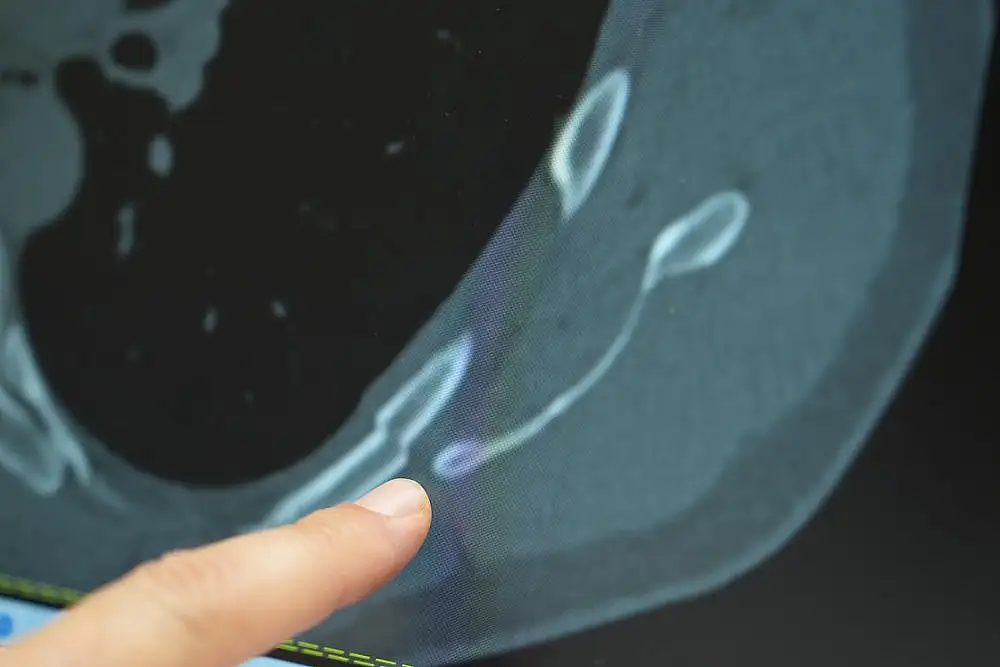

Ani başlayan ve geçmeyen göğüs ağrısı genç yaşlarda da ciddi kemik problemlerine yol açabilir diyen Göğüs Cerrahisi Uzmanı Prof. Dr. Güven Sadi Sunam, "Genç hastalarda öksürüğe bağlı kaburga kırıklarının görülme sıklığı arttı. Gençler, özellikle astımlı veya kadın hastalar göğüs ağrısıyla bize başvuruyor. Detaylı incelediğimizde bu ağrıların genellikle ani bir öksürük sonrası başladığını ve doğru tanı konulamadığını görüyoruz. Hemen detaylı bir tomografi yaparak kaburga kırığını saptıyoruz "dedi

Göğüs ağrısı şikayetiyle başvuran genç hastaların sayısında son dönemde artış yaşandığını belirten Prof. Dr. Güven Sadi Sunam, özellikle astımı olan ve stres altında yaşayan genç kadın hastalarda bu duruma daha sık rastlandığını ifade etti. Prof. Dr. Sunam, "Genç hastalar, özellikle astımlı veya kadın hastalar göğüs ağrısıyla bize başvuruyor. Detaylı incelediğimizde bu ağrıların genellikle ani bir öksürük sonrası başladığını ve doğru tanı konulamadığını görüyoruz. Hemen detaylı bir tomografi yaparak kaburga kırığını saptıyoruz" dedi